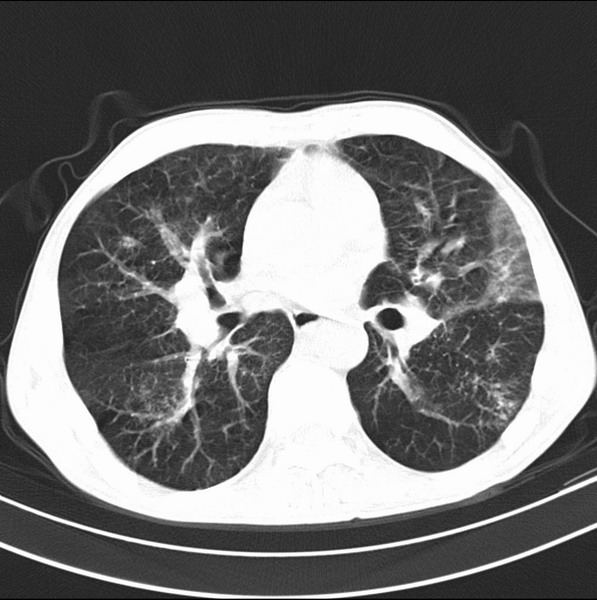

标题: CT19600:能否诊断为转移?

女、55

3年前盲肠癌、一年半前诊断膀胱癌,现在呼吸困难,临床考虑为肺转移

请问胸部ct如何诊断?能否排除淋巴管炎,纵隔窗没有问题。

考虑间质性病变,癌性淋巴管炎可能.

转移,癌性淋巴管炎。

建议抗炎后复查,不除外癌性淋巴管炎。

考虑间质性病变,癌性淋巴管炎可能.支持!

支持考虑间质性病变,癌性淋巴管炎可能.